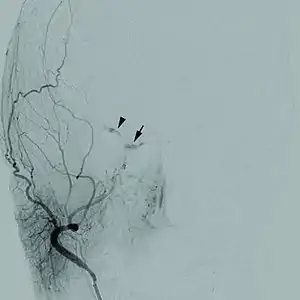

Doença cerebrovascular

As doenças cerebrovasculares são um grupo de disfunções cerebrais relacionadas com a doença dos vasos sanguíneos que fornecem sangue ao cérebro. A hipertensão arterial é a causa mais importante que pode causar danos ao revestimento dos vasos sanguíneos ( o endotélio) expondo o colágeno onde as plaquetas se juntam para dar início a um processo de reparação que nem sempre é completo e perfeito. Com a hipertensão permanente, as alterações à estrutura dos vasos sanguíneos deixando-os mais estreitos, rígidos, deformados e desiguais, sendo mais vulneráveis às flutuações da pressão arterial. Uma queda na pressão arterial durante o sono pode levar à redução acentuada do fluxo sanguíneo no estreitamento dos vasos sanguíneos, causando um acidente vascular cerebral de manhã, com um aumento súbito da pressão arterial, podendo para além disso provocar uma hemorragia intracraniana. Principalmente as pessoas que são idosas, diabéticas, fumantes ou que tenham doenças do coração têm um risco à doença cerebrovascular. Todas as doenças relacionadas com a disfunção arterial podem ser classificadas como doença macrovascular. Este é um estudo simplista pelo qual as artérias estão bloqueadas pelos depósitos gordos ou por um coágulo. Os resultados da doença cerebrovascular pode incluir um AVC, ou mesmo por vezes um acidente vascular cerebral hemorrágico. Isquemia ou outras disfunções dos vasos sanguíneos podem afectar durante um acidente vascular cerebral.